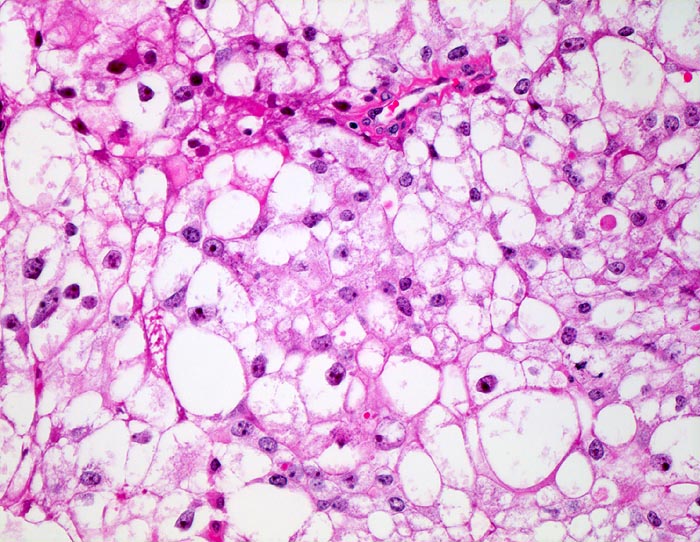

Typisch für das Nierenzellkarzinom sind relative grosse ein- oder mehrkernige atypische Zellen mit exzentrisch gelegenem Zellkern, plumpen Nukleolen und vakuolisiertem Zytoplasma. Der zytologische Nachweis wird dadurch erschwert, dass die Zellen auf ihrem Weg in die Harnblase degenerieren. Der Kern ist oftmals pyknotisch und das Zytoplasma in Auflösung und eosinophil granuliert. Differentialdiagnostisch muss an Tubulus- oder Sammelrohrepithelien gedacht werden.